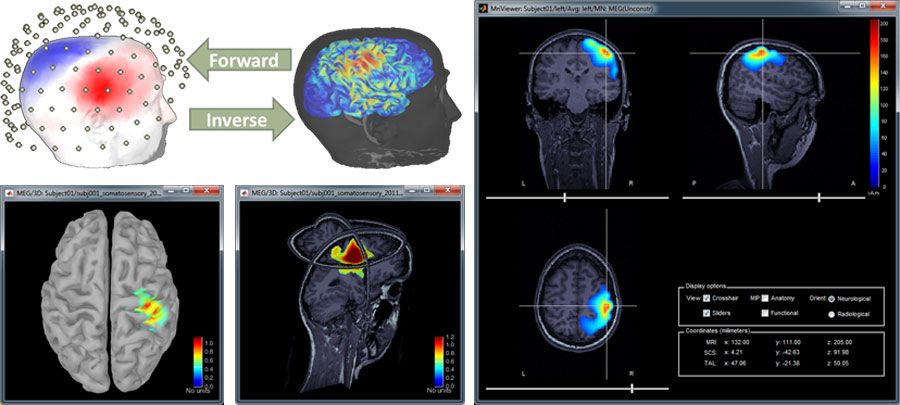

The researcher then begins reconstructing brain activity from the measured data. In this phase, Brainstorm uses forward modeling with boundary element methods (BEMs) to compute a head model by mapping neural currents and MEG/EEG sensor measurements. The researcher then uses Brainstorm’s advanced inverse modeling capabilities to locate the cortical sources that produced a specific set of MEG/EEG recordings (Figure 4).

McConnell_Brain_Figure_4_w.jpg

Figure 4. Visualizations of brain activity estimated from MEG/EEG scalp recordings.